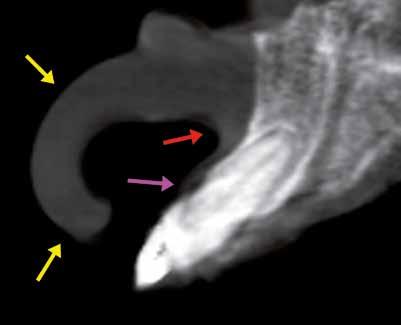

2. ábra: A felső metszőfog keresztmetszeti rétegfelvétele mutatja az ajak külső körvonalát (sárga nyilak), a gyökér csúcsát (piros nyíl) és az exponálódott foggyökeret (rózsaszínű nyíl).

Ha kihúzták a fogakat, és implantátumokat helyeztek be, már nehéz radioopak képalkotó sablont készíteni, hacsak nincsenek előkészítve a fogak a műanyag ideiglenes pótláshoz. A 2. ábrán felső kismetsző keresztmetszeti rétegképét láthatjuk. A fog az alveolushoz képest faciális elhelyezkedésben látszik, amit a szerző „anatómiai realitásnak” nevez. A gyökércsúcs

4. a ábra

területén a faciális corticalis lemez dehisztanciájára utaló jelenséget látunk (piros nyíl). A gyökér a faciális nézeten négy milliméterrel az alveoláris crestalis csont felett látható (rózsaszín nyíl). A páciens ajka az alveolus faciális felszínén és a fogon fekszik (sárga nyíl). Egy másik páciens felső szemfogának réteg-keresztmetszeti képén ugyanez a jelenség figyelhető meg (3. ábra). A fog gyökere nem mindig a legnagyobb csonttérfogatú területen van, és más szögben áll, mint az alveolus. Ez komplikációkhoz vezethet, ha az implantátum behelyezését az aktuális fogágyban tervezzük, mert a faciális corticalis lemez perforálódhat (rózsaszín nyíl). Az ajak megint az alveolus-fog-gyökér együttesen nyugszik, nehezíti a lágyszöveti vastagság és a corticalis faciális kiterjedésének a mérését. A vesztibulum labiális kiterjedése egyik keretmetszeti képen sem (2–3. ábrák) állapítható meg. A továbbfejlesztett szoftvereszközökkel kiegészített interaktív kezeléstervező szoftverek használata segít a szóródás csökkentésében, javítja a diagnosztikai képességeket, mert három dimenzióban jeleníti meg a teljes térfogatot, amely bárhonnan, bármilyen nézetből megfigyelhető. A 3D térben a „rétegenként” történő navigáció (clipping) a maxillo-mandibuláris struktúrák eddig még nem ismert vizualizációját teszi lehetővé. A 4. a–b ábrákon három dimenzióban „clippelünk” keresztül a jobb oldali szemfogon (pirossal jelölve). A 3D-ben rekonstruált kiterjedés segít meghatározni a maxilla alveolusai, illetve a fogak anatómiáját, és a gyökerek pozícióját a csont belsejében. Egy fejlett szoftvereszközzel lehetséges a szkennelt adatok szürke skálán történő küszöbértékeinek megváltoztatása. Ezt az eszközt „szelvényosztó”-nak nevezik, csökkenteni lehet vele a fémes tárgyak szórását (koronák, tömések), és az objektumokat egymástól szeparálni lehet. A szoftverszegmentációval a felső jobb oldali szemfogat virtuálisan extrahálni lehet az alveolusból, így de lehet mutatni a fogágy anatómiáját, a vékony faciális